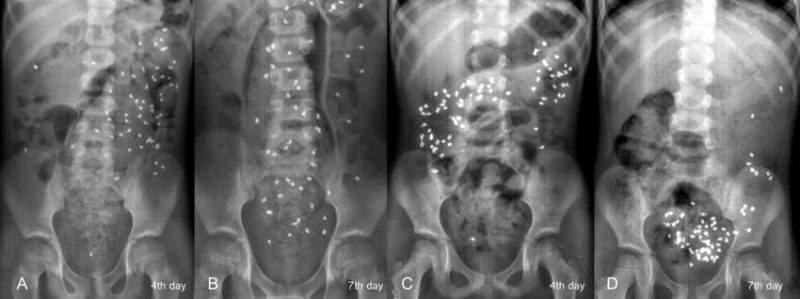

- Nghiên cứu thời gian lưu chuyển đại tràng (Colonic Transit Study): Xác định xem bệnh nhân có bị táo bón do vận động ruột chậm đi kèm hay không.